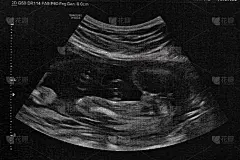

“我是来看皮肤的,为什么要做B超?”这是我们在工作过程中经常被问到的问题,今天就来科普一下。首先,大家常说的“B超”并不准确,“B超”是黑白的图像,仅反应形态的改变,现在做的都是彩超,在二维的基础上加入了彩色多普勒的功能,可以反应血流的变化。

当患者摸到皮肤有肿物时,医生的眼睛无法透过皮肤看见肿块在皮肤下的样子,而超声波可以穿透皮肤,显示包块的大小、深度、累及层次(表皮或真皮或皮下脂肪或肌肉或骨头)、边界是否清晰、有无包膜、内部回声是否均匀、囊性或实性、有无血流、周围有无大血管等,超声医生再将上述信息编辑成超声报告,从而做出囊肿、脂肪瘤、脂囊瘤、血管瘤、钙化上皮瘤、神经纤维瘤、神经鞘瘤、瘢痕疙瘩、脂膜炎、筋膜炎等诊断。此外,皮肤的鳞状细胞癌、基底细胞癌、隆突性皮肤纤维肉瘤、黑色素瘤等恶性肿瘤均有其特征性的超声表现。 当患者皮肤出现大面积红肿、溃烂、萎缩、硬化时,超声下可见真皮及皮下组织是否增厚伴水肿、血流是否增多、是否有窦道形成、浅静脉是否曲张伴血栓、动脉是否狭窄等,从而提示皮下组织水肿、脓肿、蜂窝织炎、淋巴水肿、硬斑病、血栓性浅静脉炎、化脓性汗腺炎、乳房外Paget病、蕈样肉芽肿等诊断,并测量范围,监测疾病活跃程度、判断疗效。 皮肤恶性肿瘤患者可检查相应引流区域浅表淋巴结,根据淋巴结形态是否异常,提示肿瘤是否转移。 超声检查可在皮肤上标记待手术肿物在皮下的范围,定位异常淋巴结、移植皮瓣的关键血管,皮肤浅层X线治疗(SRT)前也可标记手术切口周围腺体范围,避免影响腺体功能。 皮肤是身体的一面镜子,皮肤病变时,往往同时可能发生内脏系统病变。部分皮肤病患者需要特殊用药前,也需通过超声检查评估脏器功能状况。此时需要做肝胆胰脾肾、甲状腺、血管等常规超声检查。 通过上述内容,相信大家已经知道看皮肤为何也要做超声检查了,检查前还有一些注意事项告诉大家: 1.检查前去除纱布等覆盖物,探头必须直接接触皮肤。 2.皮肤肿物超声检查时,需要在探头涂抹大量耦合剂,并且不可用力按压,检查结果才会准确。 3.婴儿哭闹时无法检查,家长可携带安抚奶嘴、玩具等,待患儿安静后方可进行检查。 超声检查无创无辐射、价格低廉,是临床上最常用的检查手段之一。超声医生在完成检查后还需要将检查中发现的问题进行详细描述,并完成诊断报告。从检查到完成报告耗时长,需要患者理解并耐心等待。